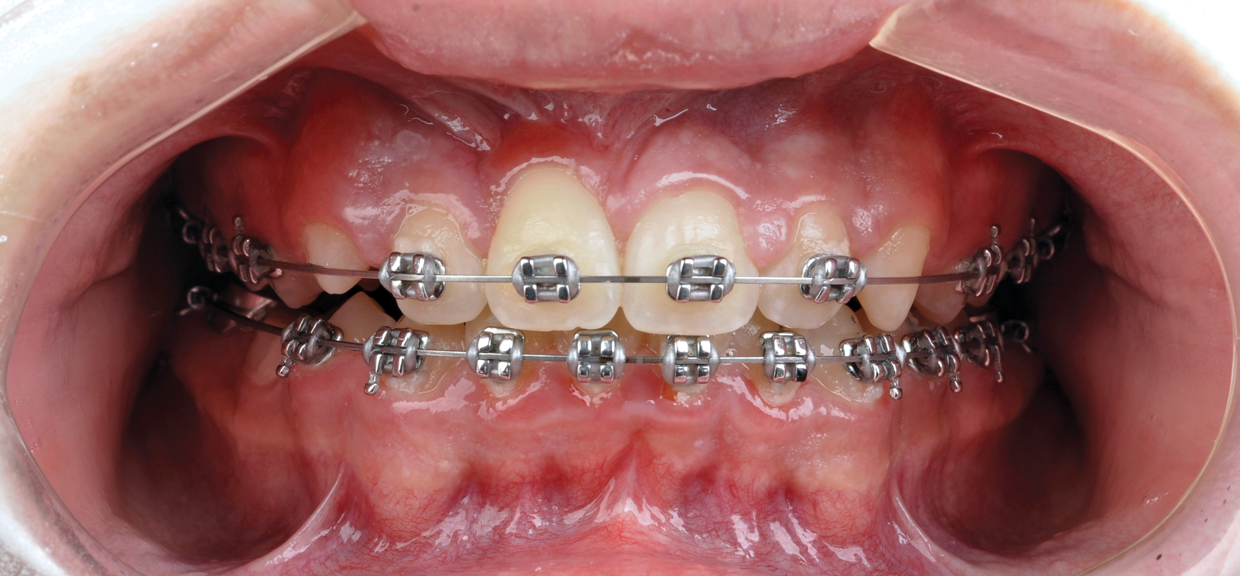

The maxillary right permanent centralincisor had a delayed eruption of 1½ years compared to its homologous incisor, and it was anteriorly displaced due to insufficient space in the premaxilla. Removal of the maxillary deciduous canines was indicated to unravel the crowding. An apically positioned flap of the impacted right central incisor was made to facilitate its eruption (Figure 5 and Figure 6). The case was worked up to plan an active phase l treatment, consisting of palatal expansion and the use of sectional fixed appliances in the upper arch. A transverse deficiency without posterior crossbite was identified, and therefore palatal expansion with a bonded expander was planned to widen the premaxilla (Figure 7 and Figure 8). A two-by-four fixed appliance system (brackets in the four maxillary anterior teeth and bands on the maxillary first molars) was used to align the maxillary teeth. The gingival margin of the retained maxillary right central incisor was slightly more apical than the left one, which erupted as expected (Figure 9 and Figure 10). Figure 11 shows a panoramic radiograph taken after completion of phase 1 treatment.

In reviewing this case more closely, the sequence usually starts with a space opening (Figure 12 through Figure 14). Palatal expansion is generally performed even without the presence of a posterior dental crossbite, as many patients with impacted maxillary central incisors are deficient in the development of the anterior portion of the maxilla.7,11 The use of sliding mechanics with open coils in conjunction with simple fixed systems is preferred to removable appliances since they deliver a light, continued force instead of an intermittent force.7 Interarch mechanics allow space to be gained for either the natural eruption or the surgical/orthodontic traction of the impacted maxillary central incisor.7 After palatal expansion, rigid structures, such as fixed transpalatal arches soldered to upper first molar bands, might first be used to anchor the active traction of the impacted tooth. Later, orthodontic fixed appliances reportedly have been used in the maxillary anterior to detail the position of the maxillary central incisor in the arch.11 Frequently, power arms are incorporated into palatal expanders.12 Fixed systems initially employ flexible nitinol wires and round stainless-steel wires. After initial leveling, rectangular stainless-steel wires have been used as part of several protocols to produce torque and place the roots of the resolved impacted central incisor in the proper position in its apical base.3,7,13 Orthodontic traction is conducted with different systems based on the preference of the clinician.3,7,10

Fig 12. After expansion of the maxillary arch, the modified palatal expander was used for traction of the impacted maxillary right central incisor. Fig 12: Palatal expansion to gain space in the premaxilla for the impacted maxillary right central incisor. Fig 13: Traction of the impacted maxillary right central incisor through a palatal orthodontic attachment and the use of a power arm incorporated in the expander. Fig 14: Detailing the position of the impacted maxillary right central incisor with orthodontic fixed appliances.

Figure 12

Fig 13. After expansion of the maxillary arch, the modified palatal expander was used for traction of the impacted maxillary right central incisor. Fig 12: Palatal expansion to gain space in the premaxilla for the impacted maxillary right central incisor. Fig 13: Traction of the impacted maxillary right central incisor through a palatal orthodontic attachment and the use of a power arm incorporated in the expander. Fig 14: Detailing the position of the impacted maxillary right central incisor with orthodontic fixed appliances.

Figure 13

Fig 14. After expansion of the maxillary arch, the modified palatal expander was used for traction of the impacted maxillary right central incisor. Fig 12: Palatal expansion to gain space in the premaxilla for the impacted maxillary right central incisor. Fig 13: Traction of the impacted maxillary right central incisor through a palatal orthodontic attachment and the use of a power arm incorporated in the expander. Fig 14: Detailing the position of the impacted maxillary right central incisor with orthodontic fixed appliances.

Figure 14